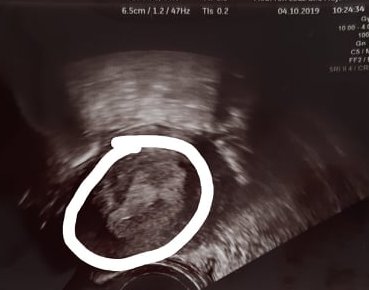

Przeraża mnie, że startuje od tak małego wyniku. Późno mi wyszedł test ciążowy, dopiero na trzeci dzień od spodziewanej miesiączki i to bladziutka. Mam regularne miesiączki a wrzesień jakiś bardzo dziwny był, wszystko opóźnione. Moje hcg:

W środę ginekolog, o ile będzie możliwe, odpuszczam betę HCG, jest to stresujące bo moje wyniki różnią się od innych. Nie mam żadnych plamień. Biorę luteinę, witaminy. Mam nadzieję, że będzie coś z tego, staramy się z partnerem o dziecko od jakiegoś czasu. Przeszłam bakterię, która poblokowała mi jajowody dlatego to zajście w ciążę, to dla mnie taki mały cud bo już się szykowałam na laparoskopię. Co uważacie? Oczywiście mam obawy co do poronienia, ciąży pozamacicznej chociaż w tamtym tygodniu miałam piękne miejsce dla zarodka w macicy.